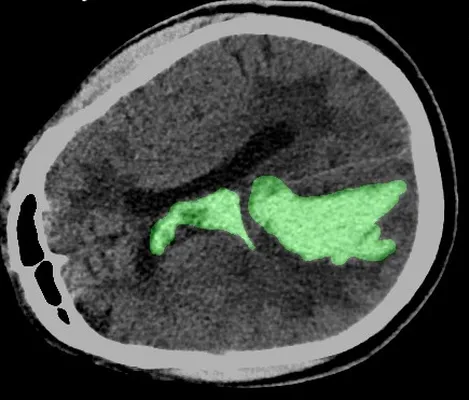

passion for innovation of AI in Medical Images, drove me to

focus my thesis on developing AI-assisted software for

classifying and segmenting intracerebral hemorrhage.